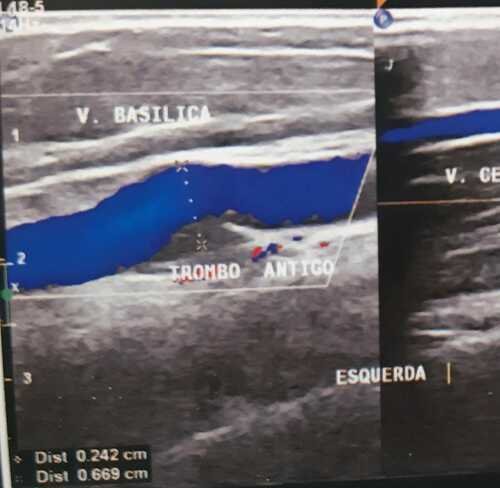

No final de Outubro de 2021 fui internada com um trombo na artéria subclávia esquerda e axila, no momento em que isso aconteceu estava aterrorizada. Ao sair do hospital, voltei para casa com um diagnóstico em aberto, confusa e ansiosa, esperando incessantemente até que o coágulo sanguíneo se desfizesse para finalmente descobrir a causa do mesmo.

Ao se passarem 3 meses, retornei ao médico com novos exames, já curada da trombose de membro superior, recebi a notícia de uma compressão arterial, mais especificamente Síndrome do Desfiladeiro Torácico. Em exames mais específicos, descobriu-se também uma Costela Cervical, que ajudou para com a compressão da artéria.